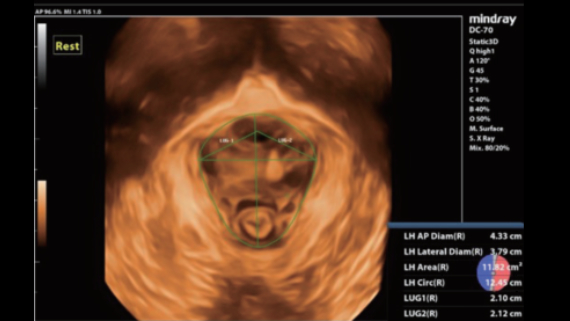

ImĂĄgenes clĂnicas